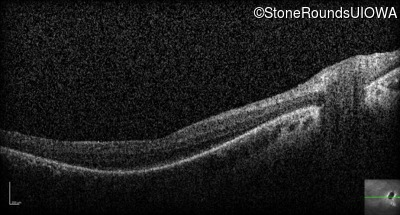

Optical Coherence Tomography - Right - 20/100

Exemplar / OCT Stack

OCT Stack